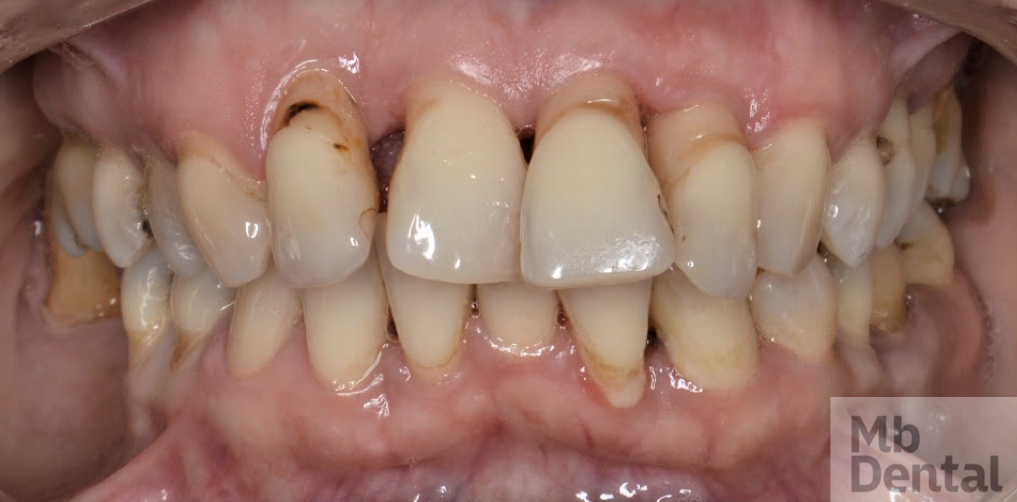

Caz sever boala parodontala

În funcție de faza în care a fost prinsă boala, dacă aceasta este acută sau cronică, dar și în funcție de gravitatea și dimensiunea pungilor parodontale, medicul dumneavoastră vă va recomanda în urma etapei de terapie inițială asocierea unor antibiotice pe o durată cuprinsă între 5 și 14 zile. În cazurile severe se poate indica asociarea a 2 antibiotice, pentru a cuprinde un spectru cât mai larg antibacterian. De asemenea, în cazurile refractare la tratament sau în cele recidivante, se va realiza o antibiogramă a secrețiilor parodontale urmată de un tratament medicamentos in functie de rezultatele acesteia.